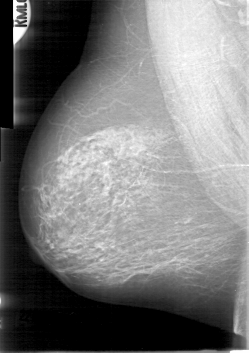

FILE: D_4014_1.LEFT_CC.OVERLAY

TOTAL_ABNORMALITIES 1

ABNORMALITY 1

LESION_TYPE MASS SHAPE LOBULATED MARGINS OBSCURED

ASSESSMENT 0

SUBTLETY 5

PATHOLOGY BENIGN

TOTAL_OUTLINES 1

BOUNDARY